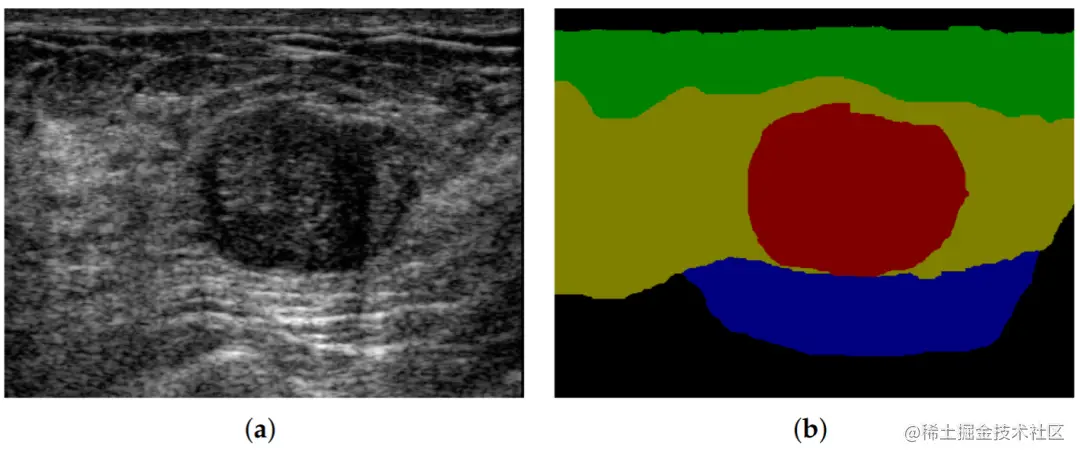

当我们看到一张图片,我们能够直接分辨出图片中的各个物体,比如人、车、建筑等等。但是对于计算机来说,要想实现这一点就需要进行语义分割。语义分割是计算机视觉领域的一个任务,它的目的是将图像中的每个像素进行分类,划分为不同的语义类别,从而更好地理解图像。

举个例子,比如下面这张图:

我们希望计算机能够自动地识别出图像中的每个像素属于哪个类别,比如蓝色的是车,红色的是人,这就是语义分割的任务。